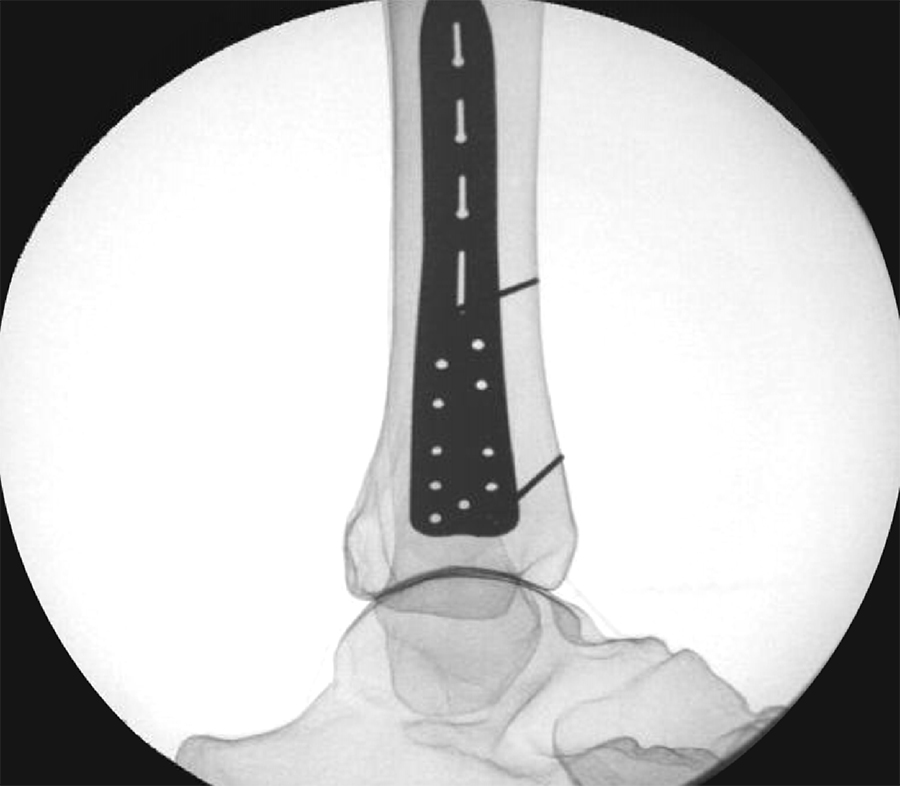

To provide an economical and effective solution, the new templates are manufactured using 3D printing technology and utilizing non-implantable stainless steel. The templates mimic the shape of the respective anatomic plates (Fig 3) and allow reprocessing for repeated use. They are radiopaque, and K-wire holes indicate the location of plate holes (Fig 4). To minimize system complexity, templates are provided for the shortest and most common length of an implant. Determination of other plate sizes can be deduced from straight measurements. The templates are labeled DO NOT BEND as they will no longer mimic the partnered implant, and repeated bending can result in template breakage.